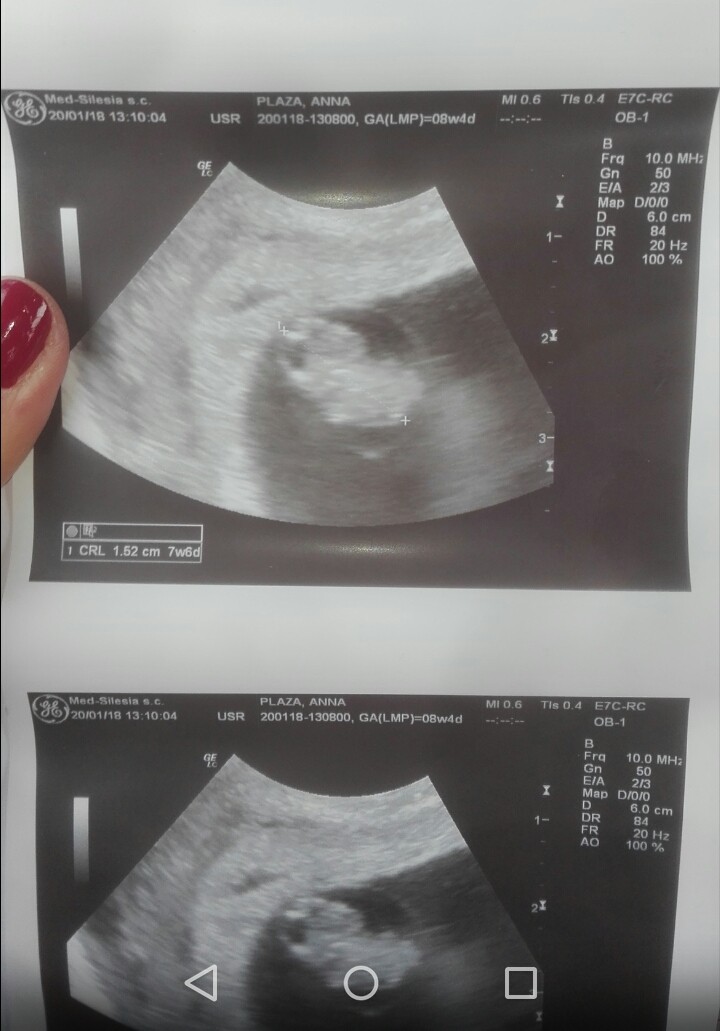

Aaaaaa popłakałam się ze szczęścia <3 groszek pomachał mi rączkami, widziałam i słyszałam serduszko, 158 uderzeń na minutę :D jest cudnie!Zobacz załącznik 836080 Zobacz załącznik 836081

Gratuluję! Piękne zdjecia!